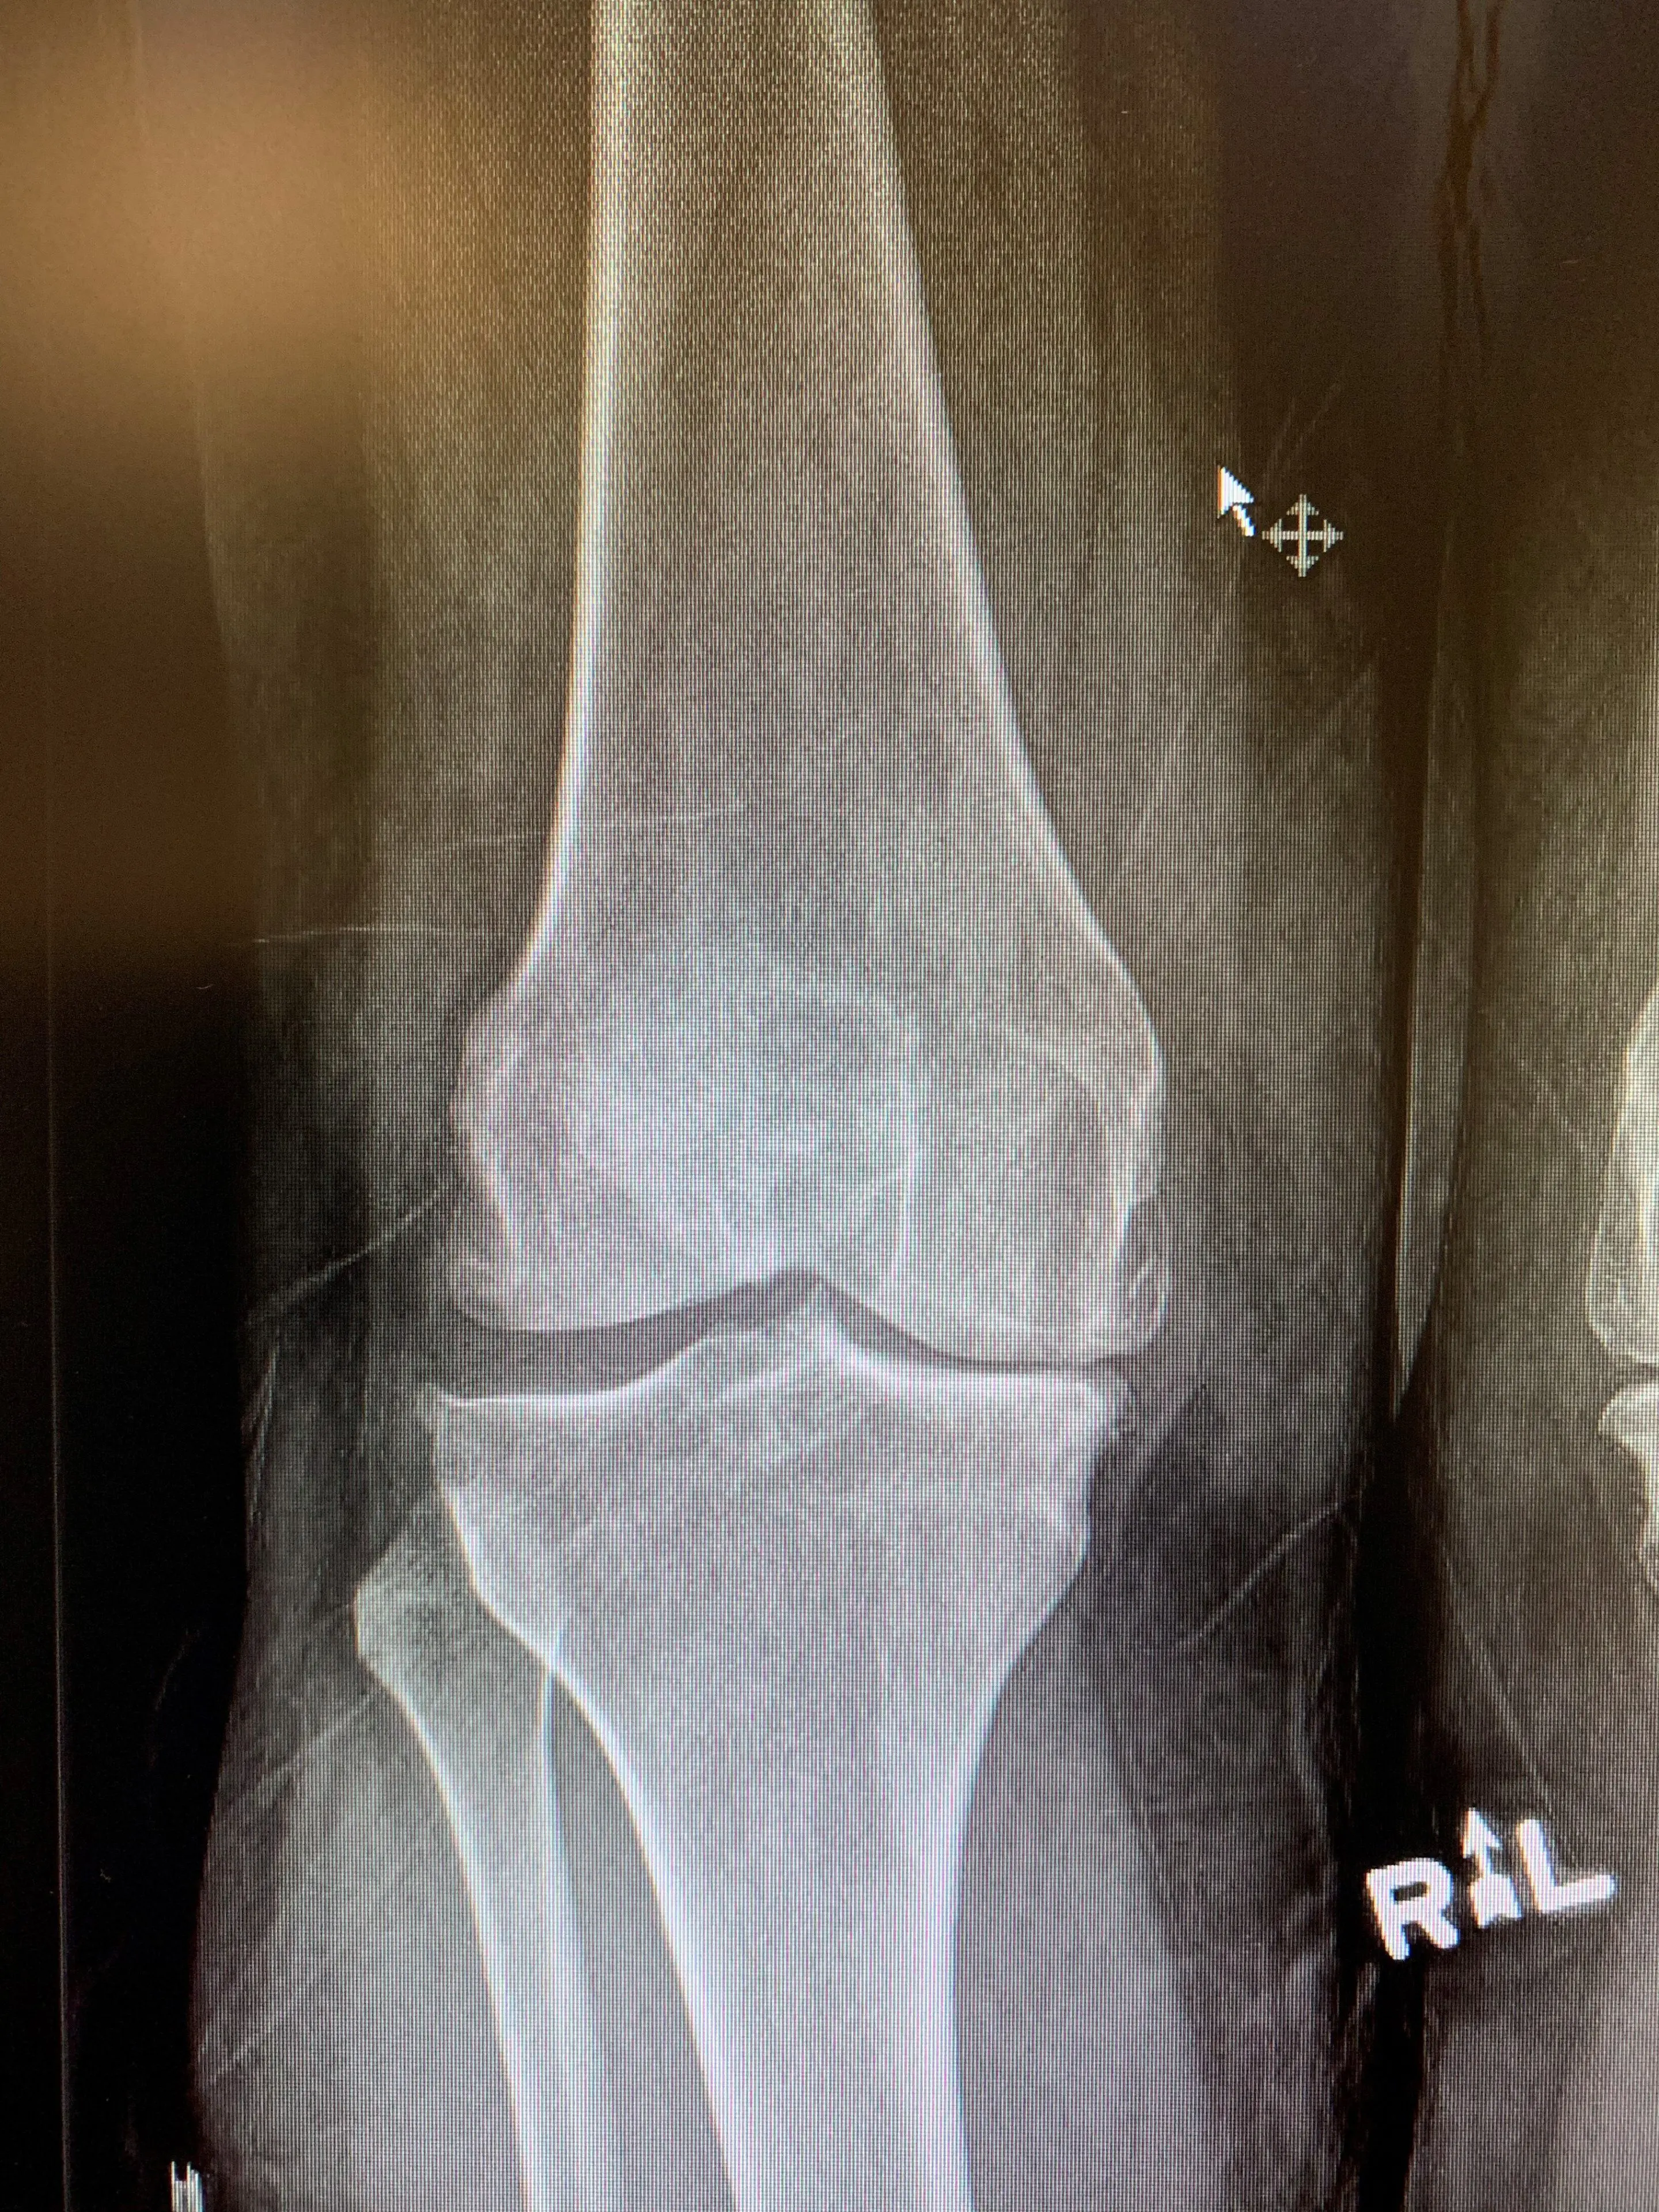

A 63 year-old male who was referred to our clinic with end-stage left knee arthritis for consideration for a Total Knee Replacement. We assessed him at our clinic, including his medical history and his suitability for surgical management of his arthritis.

Pre-op